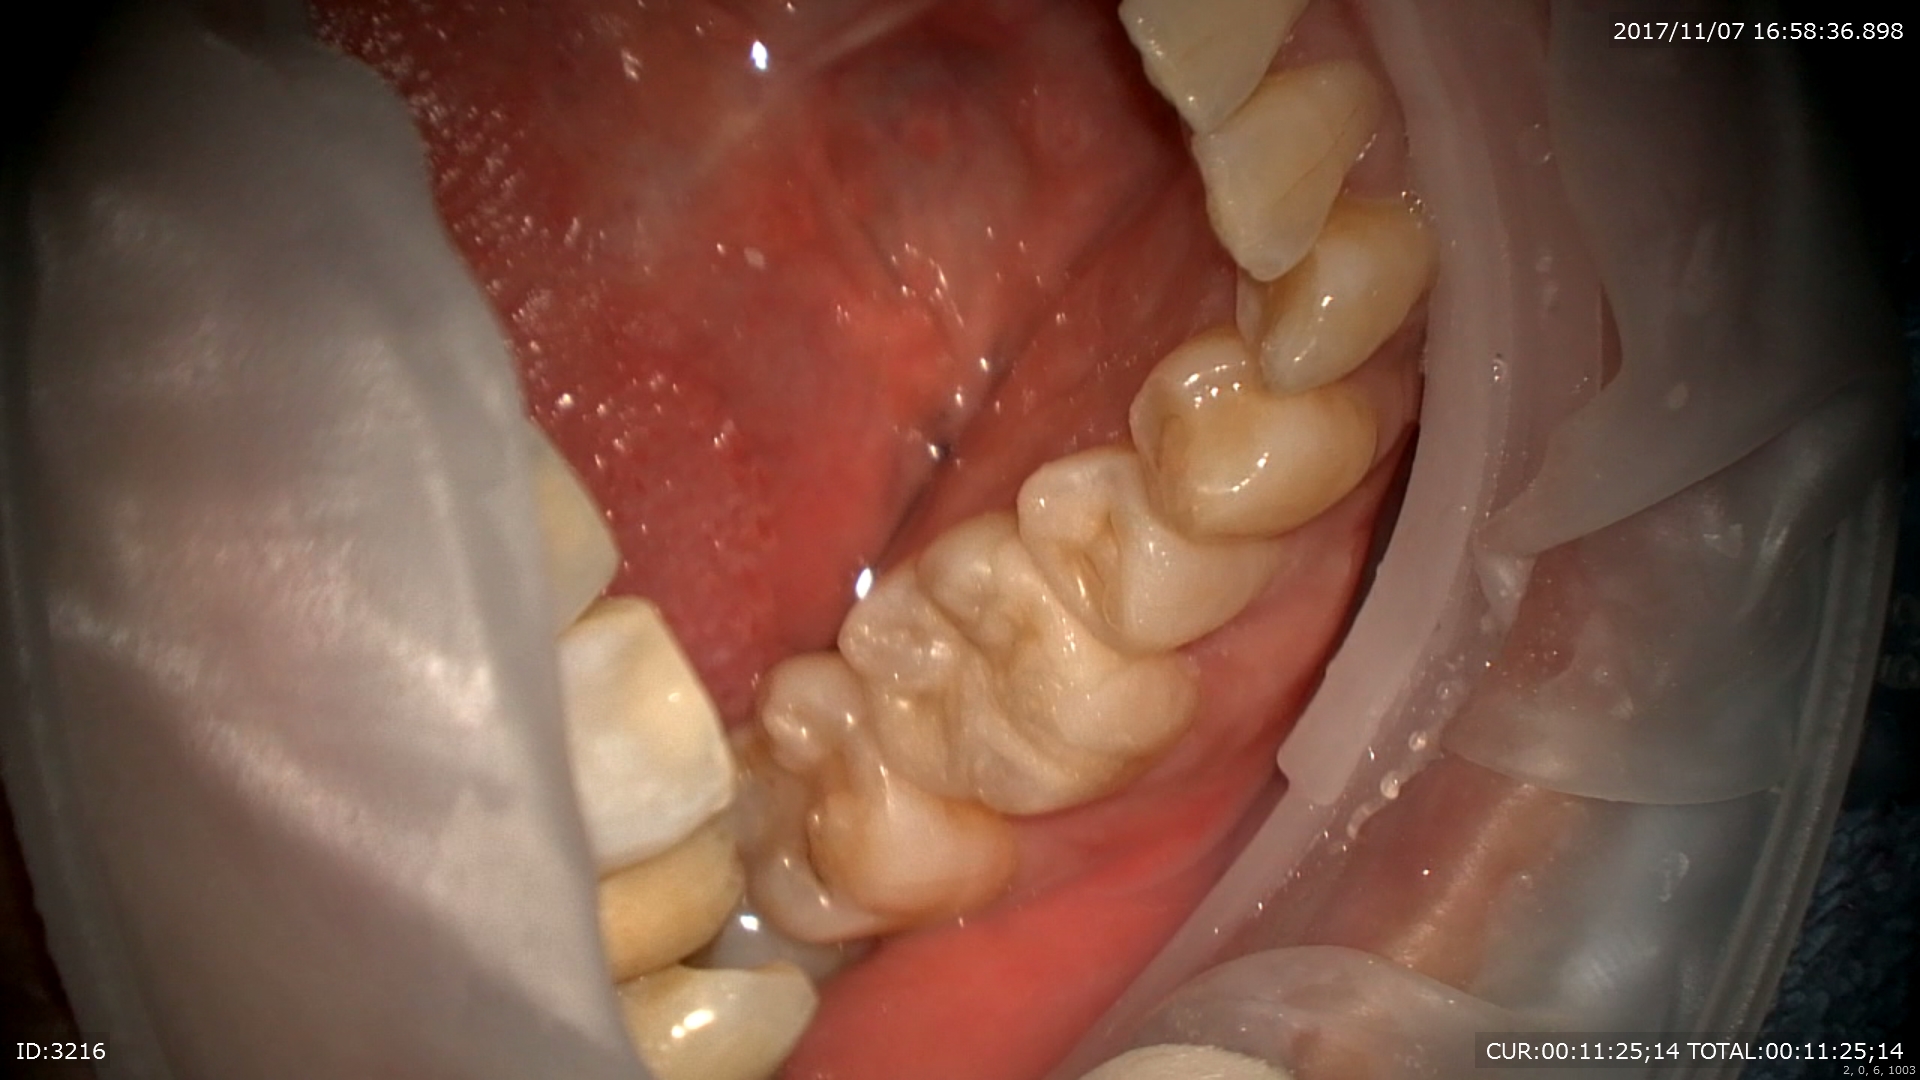

主訴:むし歯が痛い

痛そうです。

丁寧にむしばをマイクロ下で取ります。

むし歯が取りきれました。直ぐ神経です!!守らなきゃ